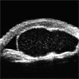

- ciliary body mass, immersion ultrasound, cystic lesion

- Ultrasonography device

- Immersion ultrasound of mass shows cystic lesion 11mm in diameter